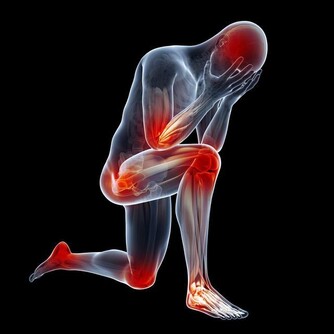

4. 你不能發揮最佳狀態

人體需要硒來形成包括穀胱甘肽過氧化物酶在內的硒蛋白,這是人體把吸收的有害毒素轉化為無害副產物的主要方式之一。

所以,缺硒會導致嚴重後果,讓你很難煥發勃勃生機。